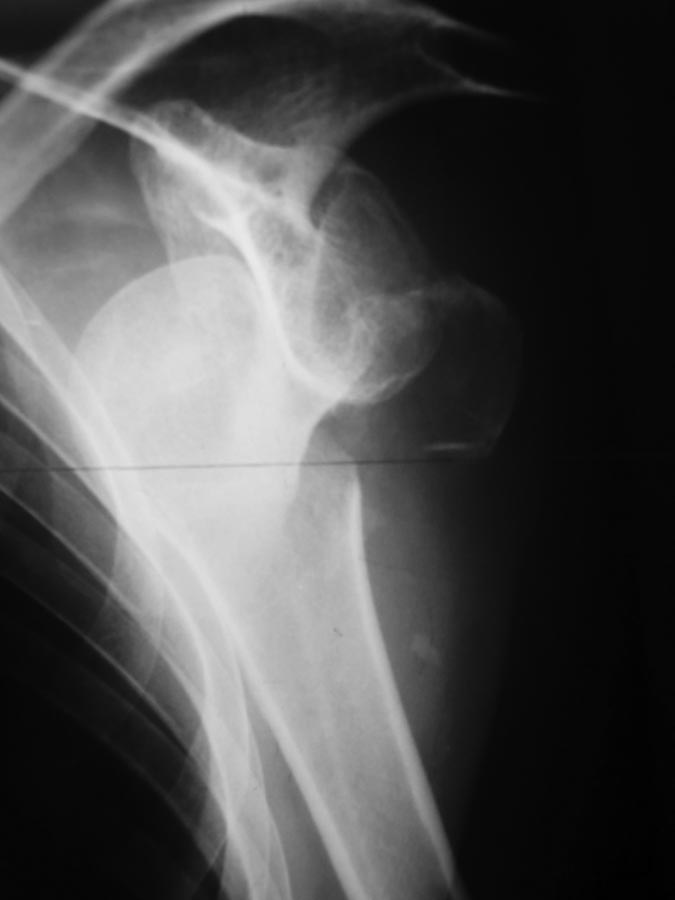

[Ortho] Застарелый вывих плеча с бугорком

Уважаемые коллеги! Хотелось бы услышать мнение по поводу лечения

05.12.16 поступил пациент 46 лет с неизвестной давностью травмы

плечевого сустава, предположительно до 10 суток. К этому времени дважды

лечился в отделении наркологии с алкогольным делирием. На следующий день

после поступления к нам диагносцирована абсцедирующая пневмония,

предположительно аспирационная. 08.12.16 производилась попытка закрытого

вправления под общим обезболиванием - без результата.

На 20.12.16 антибиотикотерапия завершена. При осмотре обращает на себя

внимание обширное кровоизлияние на половине грудной клетки со стороны

пораженной конечности. Развилась контрактура в локтевом суставе. Думаю

об открытом вправлении и фиксации бугорка, возможно сделать дупликатуру

капсулы, либо оставить как есть с дальнейшей разработкой у врачей ЛФК.

Интересует ваше мнение, коллеги.